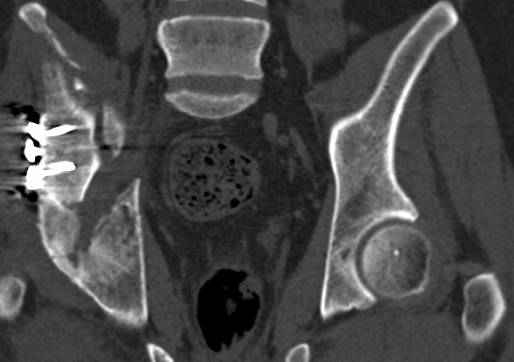

высылаю дополнительно сканы.

итак, второй вариант: высокий двухколонный с вовлечением КПС... Ни одно из основных повреждений не репонировано, кроме задней стенки. Скорее всего попытка реконструкции вертлуги сейчас будет очень травматичной и не очень эфективной, т.е. вероятный риск более значим, чем ожидаемая польза... Лучше подождать, и потом сразу эндопротез

>Вопрос к знатокам: Так что это?

к таковым себя не причисляю, но...обычное дело для нашей страны - выкладывать 3D и не показывать стандартные проекции Judet. Дигност представляет те ракурсы, которые по-его мнению наиболее информативны, более того комп сам достраивает какие-то мелкие повреждения по 3D по своему усмотрению. По данной реконструкции можно предполагать высокий двухколонный перелом с оскольчатыми передней и задней колоннами, оскольчатую высокую переднюю колонну с задним полупоперечником или одно из перечисленных с вовлечение КПС. У меня впечатление за второй вариант, но нужно обследовать нормально - проекции, сканы.